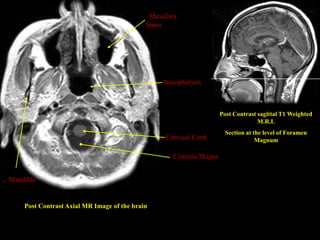

. Maxillary

Sinus

Post Contrast sagittal T1 Weighted

M.R.I.

Section at the level of Foramen

. Cervical Cord                   Magnum

Cisterna Magna

. Mandible

Post Contrast Axial MR Image of the brain